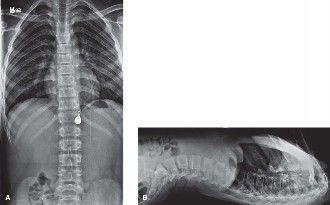

Orthopedic Management Algorithms

From a purely orthopedic standpoint, the treatment of a femur fracture in a 3-month-old is almost exclusively non-operative. The remodeling potential in this age group is nothing short of phenomenal. Infants can correct up to 30 degrees of varus/valgus angulation, 30 degrees of apex anterior/posterior angulation, and up to 1.5 to 2 centimeters of shortening.

The two primary modalities for definitive management are the Pavlik harness and the early application of a hip spica cast.

- The Pavlik Harness: For infants under 6 months of age with a proximal or mid-shaft femur fracture, the Pavlik harness is often the treatment of choice. It is exceptionally well-tolerated, allows for easier diaper changes, and has a lower risk of skin complications compared to a spica cast. The harness holds the hips in flexion and abduction. Biomechanically, this position relaxes the deforming muscle forces (specifically the iliopsoas, which flexes and externally rotates the proximal fragment, and the adductors, which pull the distal fragment medially). By aligning the distal fragment to the flexed and abducted proximal fragment, the harness acts as a dynamic tension-band, utilizing the thick periosteal sleeve to guide reduction.

- The Hip Spica Cast: If the fracture is highly unstable, extremely distal, or if there are concerns about the caregivers' ability to manage a harness (though in NAT cases, the child will likely be placed in foster care), a spica cast is indicated. Spica casting provides rigid immobilization but requires meticulous application technique to prevent skin breakdown, compartment syndrome, and unacceptable malalignment.

We apply the cast material (typically a hybrid of plaster for the initial molding layers, followed by fiberglass for structural integrity). The cast extends from the nipple line down to the toes on the affected side, and down to the knee on the contralateral side (hence, a "one-and-a-half" spica).

Radiographic Follow-up and Remodeling

Orthopedic follow-up is scheduled at 1 week, 2 weeks, and 4 weeks post-application. Radiographs are taken at each visit to ensure maintenance of reduction and to monitor callus formation. In infants, robust woven bone callus is typically visible by 10 to 14 days. Clinical union is usually achieved by 3 to 4 weeks, at which point the cast or harness can be safely discontinued.

We rely heavily on the infant's massive remodeling potential. While we strive for perfect anatomic reduction, we accept up to 30 degrees of angulation in any plane. Over the next 12 to 24 months, the bone will undergo intense osteoclastic resorption on the convex side and osteoblastic bone formation on the concave side, governed by Wolff's Law. However, it is vital to remember that while angulation remodels exceptionally well, rotational malalignment does not remodel reliably. Therefore, controlling rotation during the initial casting or harnessing is the surgeon's most critical biomechanical objective.